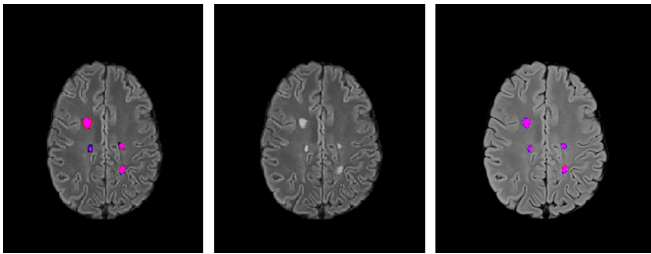

团队用两个模型验证数据质量:基于成人数据训练的2D UNet++模型取得DSC 0.541,而专用工具LST-AI的F1分数达0.714。结果显示模型对常规MS病灶识别良好(如图2),但对Balo病灶(如图1)检测欠佳,凸显儿科数据的独特性。值得注意的是,现有MS分割模型的DSC通常在0.67左右,说明当前算法在儿科数据上仍有提升空间。